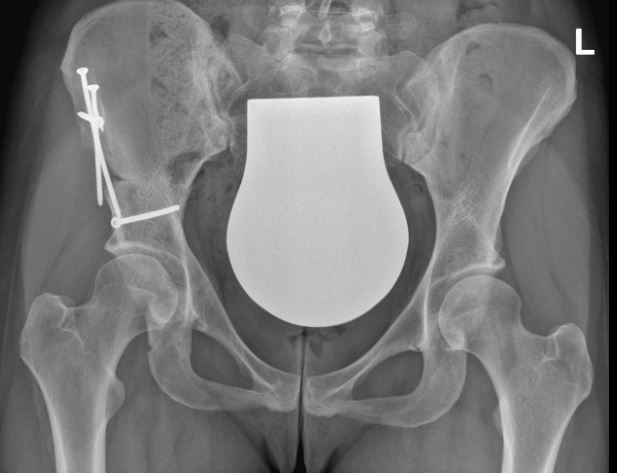

Bild: Universitätsklinik Balgrist

Bei bereits entwickelter Hüftgelenkarthrose ist die PAO nicht mehr sinnvoll. Hier ist die Implantation eines künstlichen Hüftgelenks die Therapie der Wahl.

Eine alleinige Hüftspiegelung (Arthroskopie) ist keine ursächliche Behandlung. Sie kann das Hüftgelenk destabilisieren und sollte bei einer Hüftdysplasie vermieden werden. In seltenen Fällen kann die Arthroskopie bei geringgradiger (grenzwertiger) Hüftdysplasie und femoroacetabulärem Impingement zum Einsatz kommen.